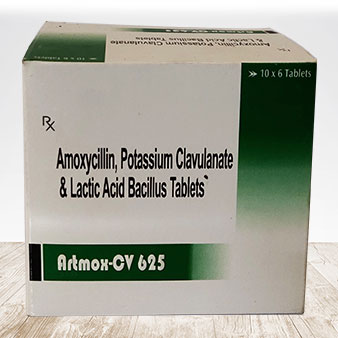

Our Values

As a third party manufacturing company, we prioritize quality, and reliability. Upholding stringent regulatory standards, ensuring product consistency, and fostering transparent communication with clients are essential. Innovation, cost-effectiveness, and a commitment to sustainable practices contribute to building trust within the pharmaceutical industry.